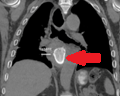

CT θώρακα. Αμφοτερόπλευρες υπεζωκοτικές συλλογές, εντονότερες αριστερά (Ευγενική παραχώρηση Dr. V. Penopoulos)